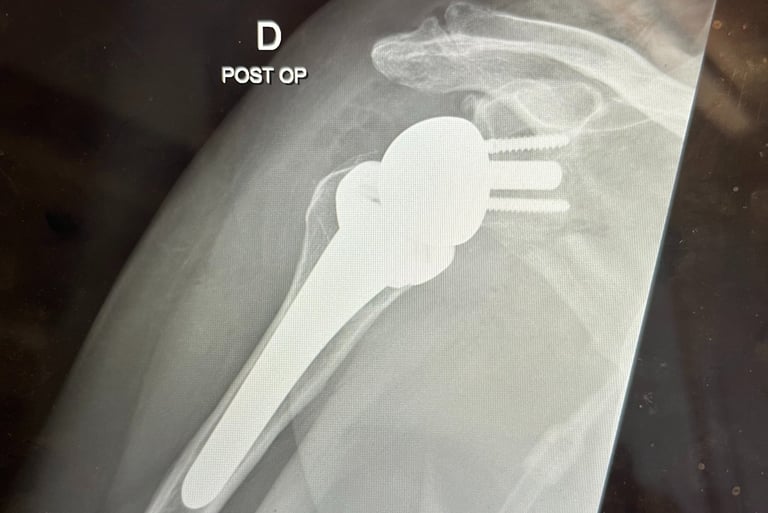

Mi occupo del trattamento delle principali patologie della spalla, con particolare esperienza nella protesica di spalla (anatomica e inversa). Tratto inoltre instabilità di spalla, lesioni della cuffia dei rotatori e traumatologia della spalla, con l’obiettivo di ripristinare la funzione articolare e ridurre il dolore attraverso tecniche chirurgiche moderne e personalizzate.